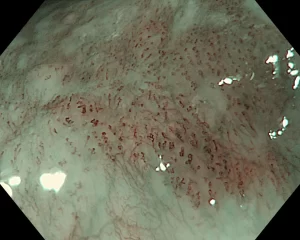

Khi sử dụng công nghệ nội soi nhuộm màu và phóng đại, bác sĩ phát hiện một tổn thương phẳng, bắt màu nâu với kích thước chỉ khoảng 15mm. Chẩn đoán cho thấy bệnh nhân bị ung thư thực quản. Nhìn được tổn thương nhỏ nhờ phóng đại 150 lần Nam bệnh nhân 63 tuổi, có tiền sử hút thuốc lá nhiều năm. Khi đi khám sức khỏe định kỳ bệnh nhân được chỉ định nội soi tiêu hóa, tầm soát ung thư vùng họng – thực quản bằng công nghệ hiện đại NBI. Khi sử dụng NBI, bác sĩ phát hiện một tổn thương phẳng, bắt màu nâu, kích thước khoảng 15mm. Tiếp đó, bác sĩ sử dụng hệ thống Olympus X1 và dây soi EZ1500 (độ phóng đại lên đến 150 lần) cho phép quan sát rõ vi mạch bề mặt. “Đánh giá vòng mạch nhú nội biểu mô (IPCL) cho thấy đây là type B1 theo phân loại JES, gợi ý ung thư biểu mô vảy thực quản giai đoạn sớm ở lớp niêm mạc, có chỉ định điều trị bằng cắt tách dưới niêm mạc qua nội soi (ESD). Tổn thương thực quản của bệnh nhân được nhuộm màu, phóng đại rất dễ quan sát (Ảnh: Bệnh viện cung cấp). Đây là một phương pháp can thiệp tối thiểu, nhằm hạn chế xâm lấn, giúp tiết kiệm chi phí, đồng thời cải thiện thời gian sống và chất lượng cuộc sống của người bệnh”, TS.BS Bùi Ánh Tuyết, Trưởng khoa Nội soi thăm dò chức năng, Bệnh viện K thông tin. Trường hợp thứ 2 là bệnh nhân nam 67 tuổi, tiền sử nghiện rượu và hút thuốc lá, được nội soi tiêu hóa trong chương trình khám sức khỏe định kỳ. Khi sử dụng hệ thống nội soi Olympus X1 với công nghệ NBI, bác sĩ phát hiện một tổn thương kích thước khoảng 10mm tại thực quản. Dựa trên hình ảnh nội soi và kinh nghiệm chuyên môn trong đánh giá ung thư sớm, bác sĩ chẩn đoán tổn thương đã vượt quá chỉ định điều trị qua nội soi. Bệnh nhân được khuyến cáo phẫu thuật. Kết quả mô bệnh học xác định bệnh nhân mắc ung thư biểu mô thực quản đã xâm lấn vào lớp dưới niêm mạc, không phù hợp với các phương pháp can thiệp nội soi. TS Tuyết cho biết, đây là hệ thống máy nội soi mới nhất mới được bệnh viện trang bị, với chức năng nhuộm màu ảo cùng phóng đại hình ảnh quang học tới 150 lần cho chẩn đoán chính xác tổn thương ung thư và can thiệp các tổn thương một cách chính xác. Phát hiện sớm, tỷ lệ sống trên 5 năm đạt 90% Theo chuyên gia này, ung thư thực quản thuộc top 15 những bệnh ung thư thường gặp tại Việt Nam, với khoảng hơn 3.600 ca chẩn đoán mới và 3.470 ca tử vong mỗi năm. Phần lớn bệnh nhân ung thư thực quản được phát hiện ở giai đoạn muộn với các triệu chứng rõ ràng như nuốt vướng, nghẹn tăng dần, ho khàn tiếng do khối u xâm lấn vào tổ chức lân cận. Ở giai đoạn này thường không thể phẫu thuật được, điều trị hóa xạ trị đồng thời thường được chỉ định nhưng tiên lượng không quá khả quan. Việc phát hiện muộn khiến hiệu quả của việc chữa bệnh bị giảm rất nhiều. Chẩn đoán bệnh ở giai đoạn sớm có vai trò quyết định trong điều trị và tiên lượng bệnh lý ung thư thực quản giúp tăng hiệu quả và giảm chi phí điều trị. Theo nhiều nghiên cứu tại Nhật Bản, tỷ lệ sống sau 5 năm của nhóm bệnh nhân phát hiện sớm có thể đạt trên 90%.” Ung thư thực quản sớm là tổn thương ung thư khu trú tại lớp niêm mạc và dưới niêm mạc, chưa xâm lấn vào cơ thực quản. Trước đây, việc chẩn đoán ung thư thực quản chủ yếu dựa vào nội soi xác định tổn thương và sinh thiết làm xét nghiệm mô bệnh học. Tuy nhiên, nội soi ống mềm với ánh sáng trắng thường khó phát hiện được tổn thương sớm tại thực quản do tổn thương nhỏ và có màu sắc tương đối đồng nhất với niêm mạc xung quanh. Vì thế, việc sử dụng nội soi nhuộm màu phóng đại lên tới 150 lần, giúp hình ảnh sắc nét, hiển thị rõ tổn thương dù là nhỏ nhất, giúp phân tích rõ ràng vi cấu trúc và vi mạch máu của tổn thương, đưa ra nhận định chính xác về tính chất tế bào học của tổn thương, phân biệt tổn thương ung thư và không ung thư từ đó đưa ra hướng can thiệp kịp thời cho người bệnh. “Mục đích của nội soi phóng đại là giúp phát hiện sớm và phân biệt các tổn thương ung thư đường tiêu hóa thường gặp ở dạ dày, thực quản, đại trực tràng.”, TS.BS Bùi Ánh Tuyết, Trưởng khoa Nội soi thăm dò chức năng cho biết. Đặc biệt, việc ứng dụng các công nghệ xử lý hình ảnh tiên tiến để chẩn đoán và phân loại ung thư thực quản không chỉ đơn thuần là để tầm soát, phát hiện ung thư ở giai đoạn sớm mà mục tiêu chính là điều trị tổn thương ung thư ở ngay giai đoạn sớm bằng can thiệp qua nội soi. TS Tuyết khuyến cáo, nếu như trước đây, người mắc ung thư thực quản thường gặp ở độ tuổi trên 50 thì giờ đây căn bệnh này có xu hướng gia tăng và trẻ hóa. Vì thế, việc khám sức khỏe định kỳ, tầm soát phát hiện sớm để điều trị kịp thời là rất quan trọng. Để phòng ngừa ung thư thực quản, mọi người nên hạn chế ăn nhiều thịt, chất béo có nguồn gốc từ đạm động vật; bổ sung